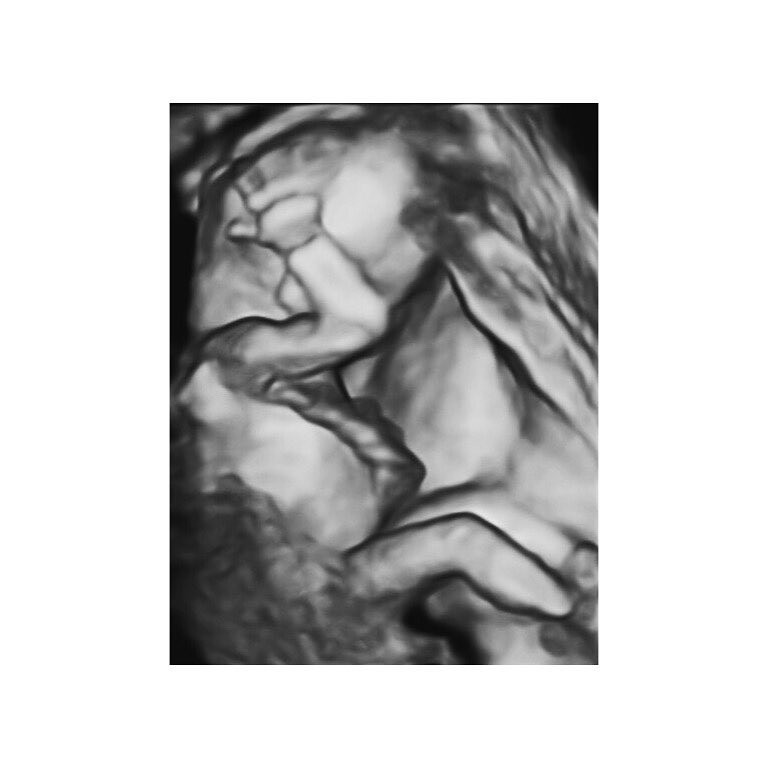

自從懷孕以來,很常可以看到自稱「拎太太」的丁文琪透露出懷孕的喜悅。丁文琪曾分享看到「兒子嘟嘟嘴」的照片,她發文:「立刻笑出來轉頭跟先生說:『好像你欸!』的同時,眼淚就從臉頰滑下來。」為人母的喜悅,正是如此吧。